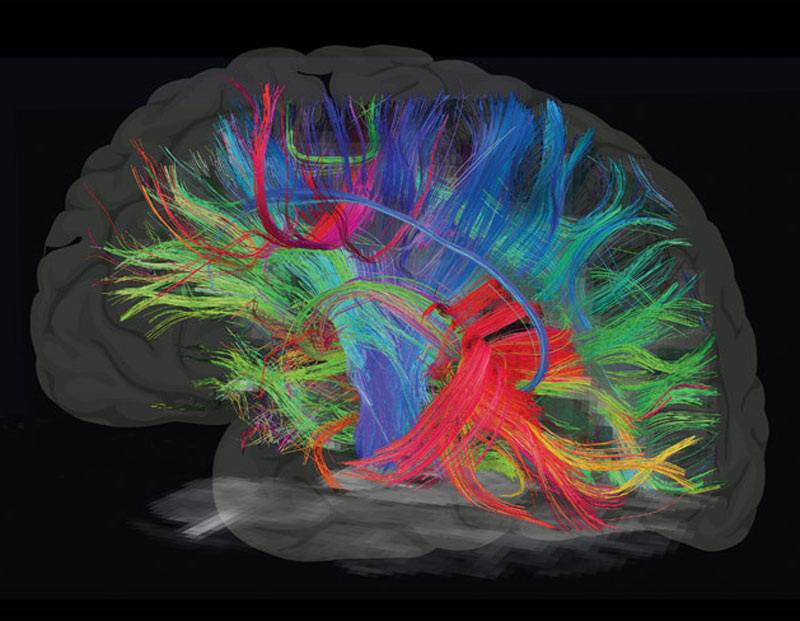

Отделению нейрохирургии Пироговского Центра исполнилось 8 лет. За это время его специалисты прооперировали около 10 тысяч пациентов. Ежегодное число операций за время работы отделения выросло с 400 до 2,5 тысяч в год. Здесь развивается несколько уникальных технологий и методов лечения пациентов с эпилепсией, опухолями головного мозга и дегенеративными заболеваниями позвоночника. Ежегодно около 400 пациентов с эпилепсией проходят предхирургическое обследование.

С 2021 г. в Лаборатории диагностики и лечения эпилепсии Отделения нейрохирургии стационара стали проводить радиочастотную термодеструкцию выявленных эпилептогенных очагов одновременно с проведением инвазивного стерео ЭЭГ мониторирования.

Пироговский Центр в сотрудничестве со Сколковским институтом науки и технологий, ООО «Сбермедии» и ООО «Иммерсмед» продолжил исследовать возможности применения цифровых инноваций в медицине. Ведутся проекты по использованию современных технологий, включая машинное обучение, для обработки результатов магнитно-резонансной томографии и электроэнцефалографии. Цель проекта — изучение причин и своевременная диагностика эпилепсии, что позволит не только приоткрыть тайны функциональных структур головного мозга, но и вовремя начать прием наиболее подходящих медикаментов, провести нейрохирургическую операцию, повысив тем самым вероятность полного излечения пациентов.

В Пироговском Центре создана соответствующая мировым требованиям эпилептологическая служба:

- Мультидисциплинарная команда (врачи разных специальностей, инженеры, лингвисты, математики и аналитики, специалисты IT)

- Высокотехнологичная нейрохирургическая служба

- Современная нейрофизиологическая лаборатория

- Передовая анестезиологическая служба

- Современная нейровизуализация (МРТ, ОФЭКТ, SISCOM)

Внедрен современный протокол диагностики эпилептогенных очагов головного мозга — протокол SISCOM (Subtraction Ictal SPECT Co-Registered to MRI)

Внедрение хирургического лечения эпилепсии с роботизированным инвазивным нейромониторингом